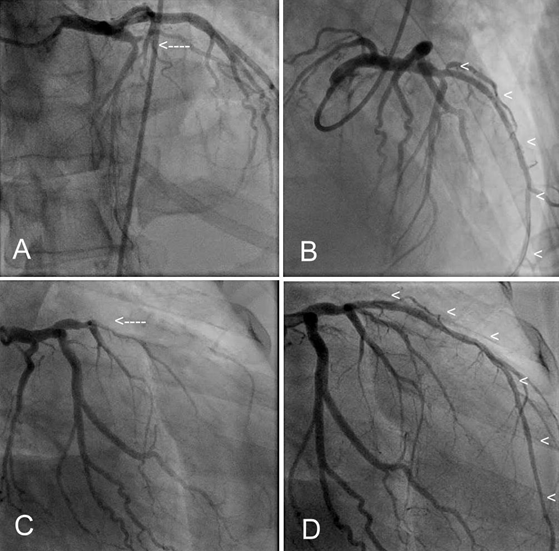

Figure 2. Coronary angiograms showing the left anterior descending coronary artery before (single arrow) and after successful stenting (arrow heads) with a bare metal stent; in the cranial (panel A and B) and caudal (panel C and D) angulation views. Note the left circumflex coronary artery without significant disease and the large LAD vessel after revascularization (arrow heads).

Emergent cardiac catheterization revealed total thrombotic occlusion of the mid left anterior descending coronary artery (Figure 2A and 2C). The remaining coronary arteries revealed only luminal irregularities; left ventriculography showed a severely decreased left ventricular ejection fraction of about 15%. Successful manual thrombectomy followed by bare metal stenting was performed (Figure 2B and 2D).